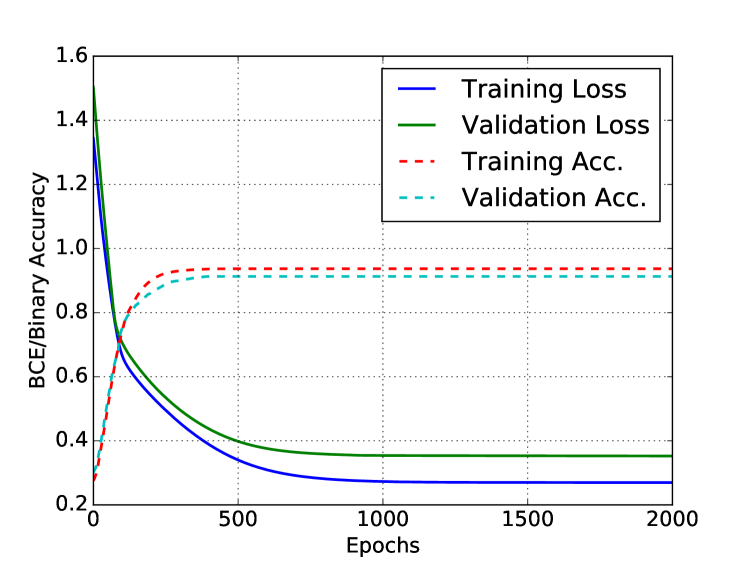

We create sub-images comprising of nodes (batch) from each image and derive the corresponding adjacency matrices to reduce memory footprint during the training procedure. Parameters of the MFN are learned by minimizing the BCE loss in (8) computed using all batches of all images in the training data using back-propagation with Adam optimiser with recommended settings [8]. To further reduce computational overhead we restrict the neighbourhood of each node to be nearest neighbours based on Euclidean distance of their locations in the image data. Based on initial investigations of ELBO we set the number of layers in MFN, . The learning curves for loss and binary accuracy are shown in Figure 1, along with the ELBO plot showing the successive increase in ELBO with each iteration within an epoch (as guaranteed by MFA) and with increasing epochs (due to gradient descent).